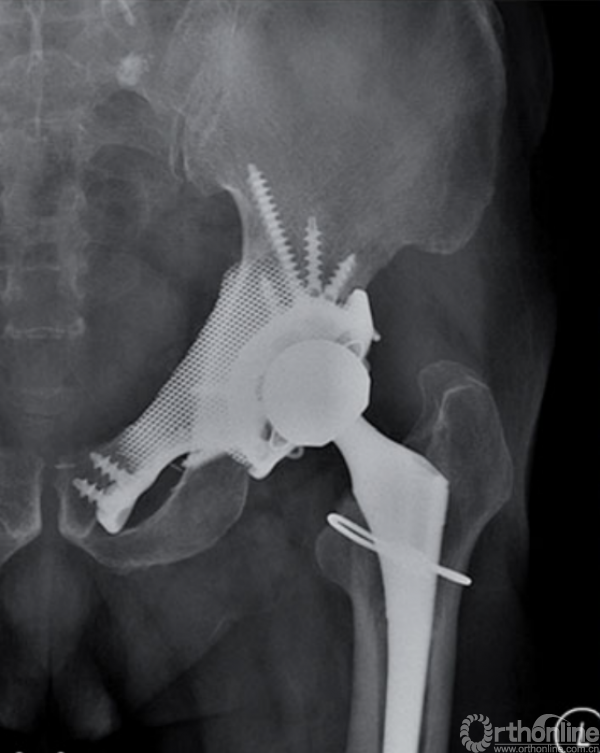

自1971年第一例定制化半骨盆假体投入临床应用起,其设计理念及方法一直在快速发展[16]。随着3D打印技术的应用以及假体设计进一步改良,定制化半骨盆假体的预后已经得到了长足进步[17-26](图4)。

但这种假体设计仍存在可以改善的地方,比如一体化设计以及重建完整骨盆环。一体化设计可从整体考虑假体力学分布及传导,重建完整骨盆环可获得骨盆三维稳定进而增强假体稳定性,避免后期的假体移位、松动及断裂[20, 27]。目前来看,具备这两种性质的定制假体仅由Wong等人报道过,但其应用仅为一例骨缺损较小的病例,并且骨盆连续性尚未被完全破坏[28]。

图4 3D打印定制化半骨盆假体